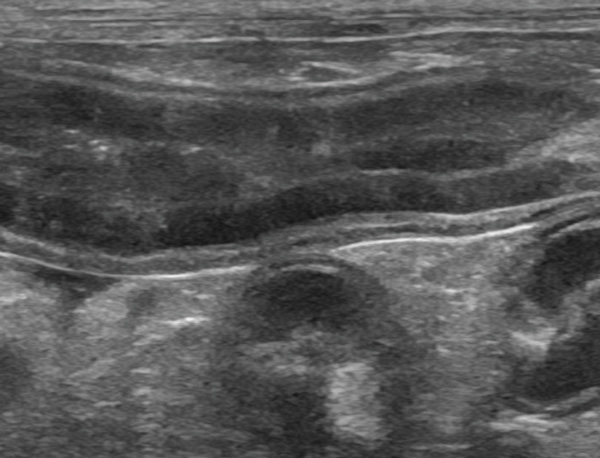

Figure 3: Example Case I, ultrasound examination of the jejunum. Note the evidence of dilated lacteals (red arrows) and a subjective reduction on the definition of intestinal wall layering. Courtesy: University College Dublin Diagnostic Imaging Service.